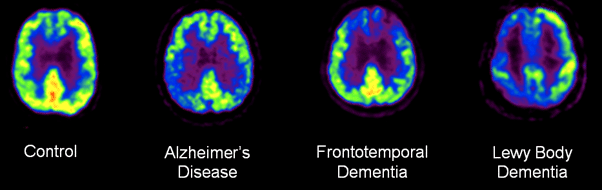

18 F-Fluorodeoxyglucose PET showing variations in Alzheimer and Dementia

PET scan indicating changes in brain glucose metabolism (shown in red and yellow). More prominent in AD indicated by brain tissue with diminished metabolic activity.